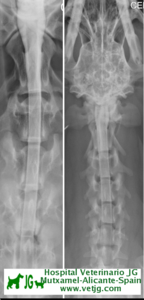

Radiografía con contrastes: mielografía por cisterna magna

RADIOGRAFÍA